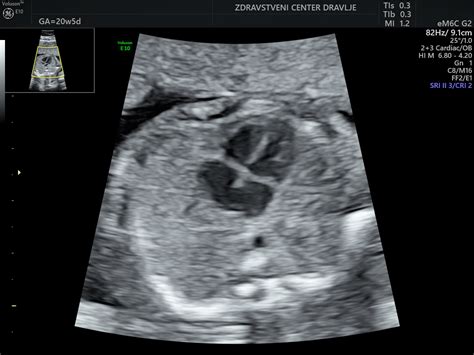

- Ultrazvočni pregledi: V tem obdobju se lahko opravijo dodatni ultrazvočni pregledi za oceno rasti in kondicije ploda, količine plodovnice, zrelosti posteljice in pretoka krvi skozi popkovnične žile.

Pričakovanje 30. Teden Nosečnosti: Plodni Mehur v Zadnji Fazi

Ko se približujemo 30. tednu nosečnosti, se plodni mehur (ali bolje rečeno, plod v maternici) nahaja v ključni fazi razvoja. To je čas, ko se telo nosečnice intenzivno pripravlja na porod, medtem ko se plod še naprej razvija in pridobiva na teži.